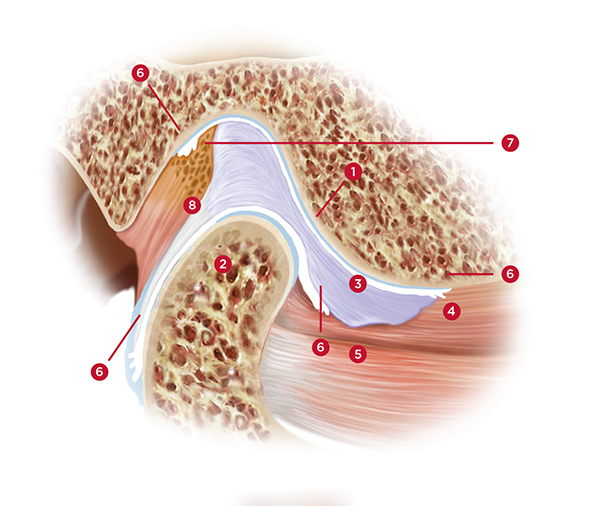

(1.) Lateral view of cross-section through the TMJ: [1] Posterior slope of the eminentia; [2] condyle; [3] disc; [4] superior lateral pterygoid muscle; [5] inferior lateral pterygoid muscle; [6] synovial tissue; [7] retrodiscal

tissue; [8] posterior ligamentous attachment of disc to condyle.

Figure 1

Also, constant tension within the superior belly of the lateral pterygoid muscle (the portion of the lateral pterygoid with attachments to the articular disc) will result in continuous stretching of the ligaments that attach the disc to the posterior surface of the condyle. This constant stretching can eventually create an unstable condyle-disc assembly, resulting in a disc that can click or pop off of and onto the lateral pole of the condyle during function (Figure 1).18 Further damage can be created if the medial aspect of the disc slides forward and off of the condylar head. This severe situation can result in the head of the condyle pressing against the highly innervated and vascular retrodiscal tissue. This can be experienced as extreme pain in the joint whenever the patient attempts to close their mandible or bite into food. If left untreated, this could eventually lead to bone-on-bone contact between the head of the condyle and the eminence and potential degeneration of the condylar head.19